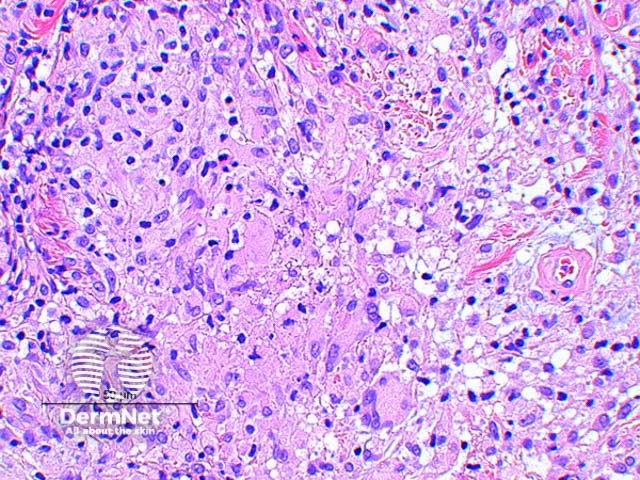

The histologic findings of Mycobacterium marinum infection vary by the age of the lesion. Scanning power view of well developed lesions demonstrate a granulomatous dermatitis (Figure 1), forming an extensive inflammatory nodular infiltrate within the dermis. Early lesions may show an acute suppurative inflammatory process with little granuloma formation. The epidermis may show prominent pseudoepitheliomatous hyperplasia with or without ulceration. There are tuberculoid granulomas with varying degrees of abscess formation (Figure 2). The infiltrate is mixed lymphohistiocytic with multinucleated giant cells and scattered neutrophils (Figures 3 and 4).

Figure 4